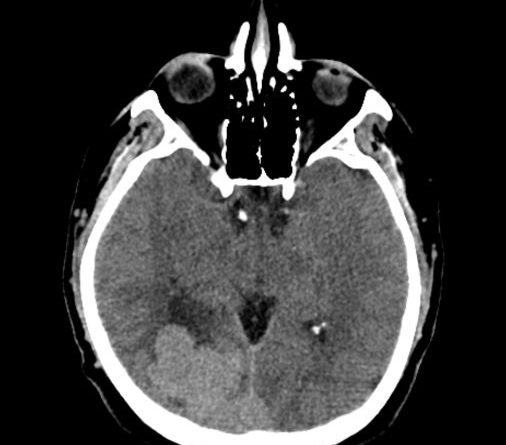

44 yaş, E

Baş ağrısı

hemorajik glioblastoma multiforme (GBM, WHO Grade 4)